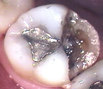

Broken / Fractured tooth. A tooth that has broken is usually too weak to hold a filling. A crown will hold the tooth together and prevent it from breaking again. If the fracture involves the nerve, Root Canal Therapy may be required before the tooth is crowned. In some cases, a broken tooth cannot be saved and must be extracted.

Broken toothThis patient chose not to have the cracked tooth above crowned, and it later fractured. This tooth had to be extracted because it cracked all the way to the root.